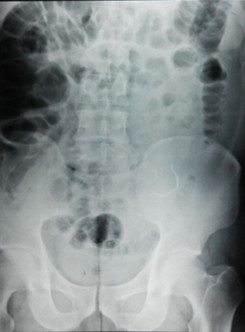

查体:腹部平软,左下腹轻压痛,未触及包块,肛门括约肌松弛,直肠内未触及异物,指套无染血。 辅查:腹部立位透视见左下腹部金属异物。腹部CT见下图。